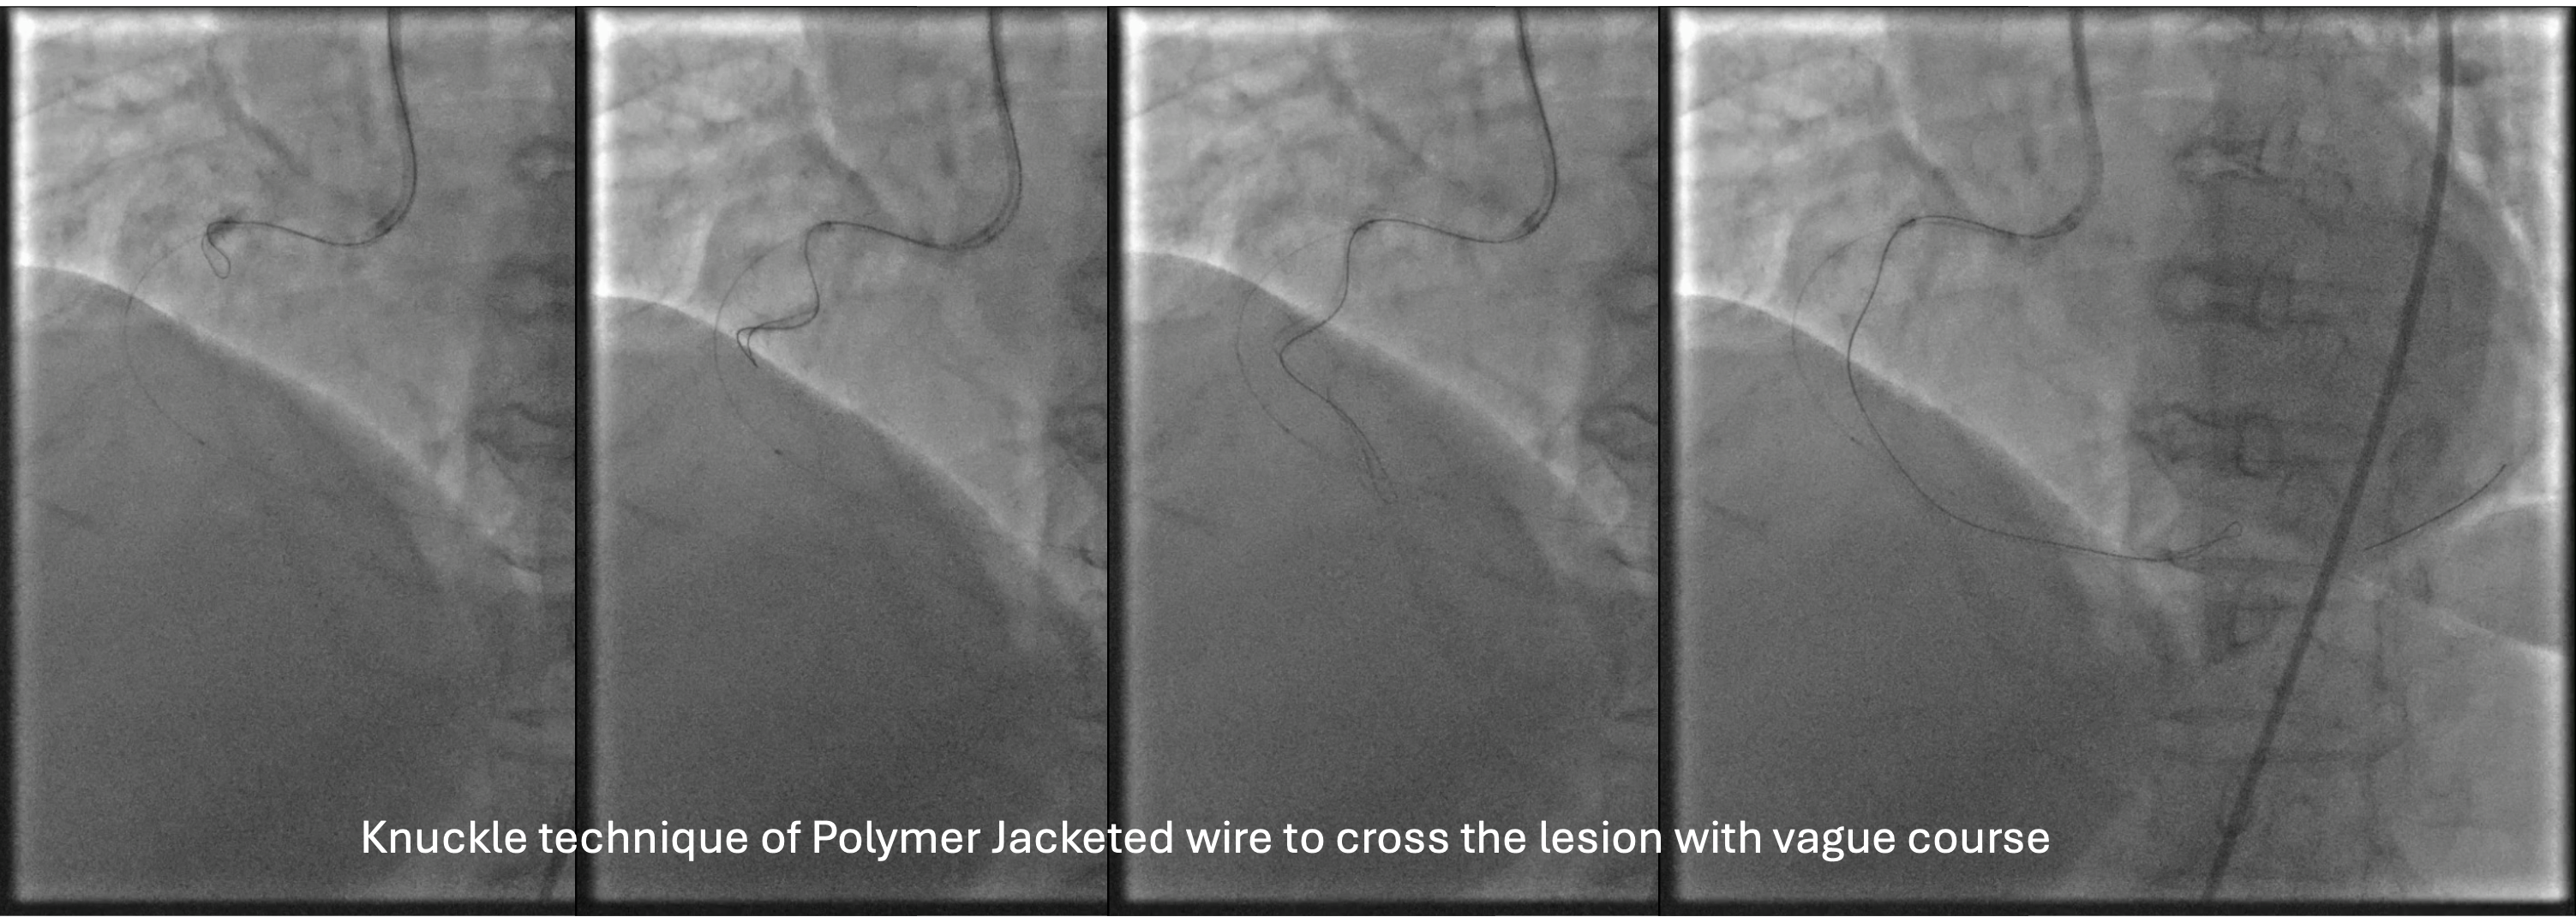

Several attempts to cross the lesion with workhorse wire and polymer jacketed wire with microcatheter support were failed because the wire went into small branch proximal to the occlusion. Guide catheter AL 0.75/7F was exchanged for JR 3.5/7F because of frequent pressure damping associated with deep engagement. Workhorse wire was left at the small branch while the second stiff wire was attempted to cross. The stiff wire (Gaia 2nd wire) and microcatheter was successfully cross and advanced to the distal. Microcatheter tip injection revealed contrast leakage to pericardial cavity. The stiff wire was exchanged for less traumatic workhorse wire and microcatheter was left to tampon the coronary perforation. Due to vague course of the vessel, rewiring to RCA was done with polymer jacketed wire in knuckle technique that eventually succeeded to cross the lesion and enter the true lumen. Pre-dilatation with semi-compliant balloon 2.5x15 mm at proximal-mid RCA was done to restore the flow. Angiography revealed tortuous and calcified RCA with some contrast leakage confined to pericardium. Subcutaneous fat embolization was attempted several times to seal the perforation. With minimal residual leakage, pre-dilatation with non-compliant balloon 3.0x18 mm was proceeded. Stent DES 3.0x38 mm was implanted at the proximal-mid RCA with the aid of 6F guide extension catheter. Angiography evaluation demonstrated good PCI result leaving only minimal residual contrast leakage confined to pericardium.